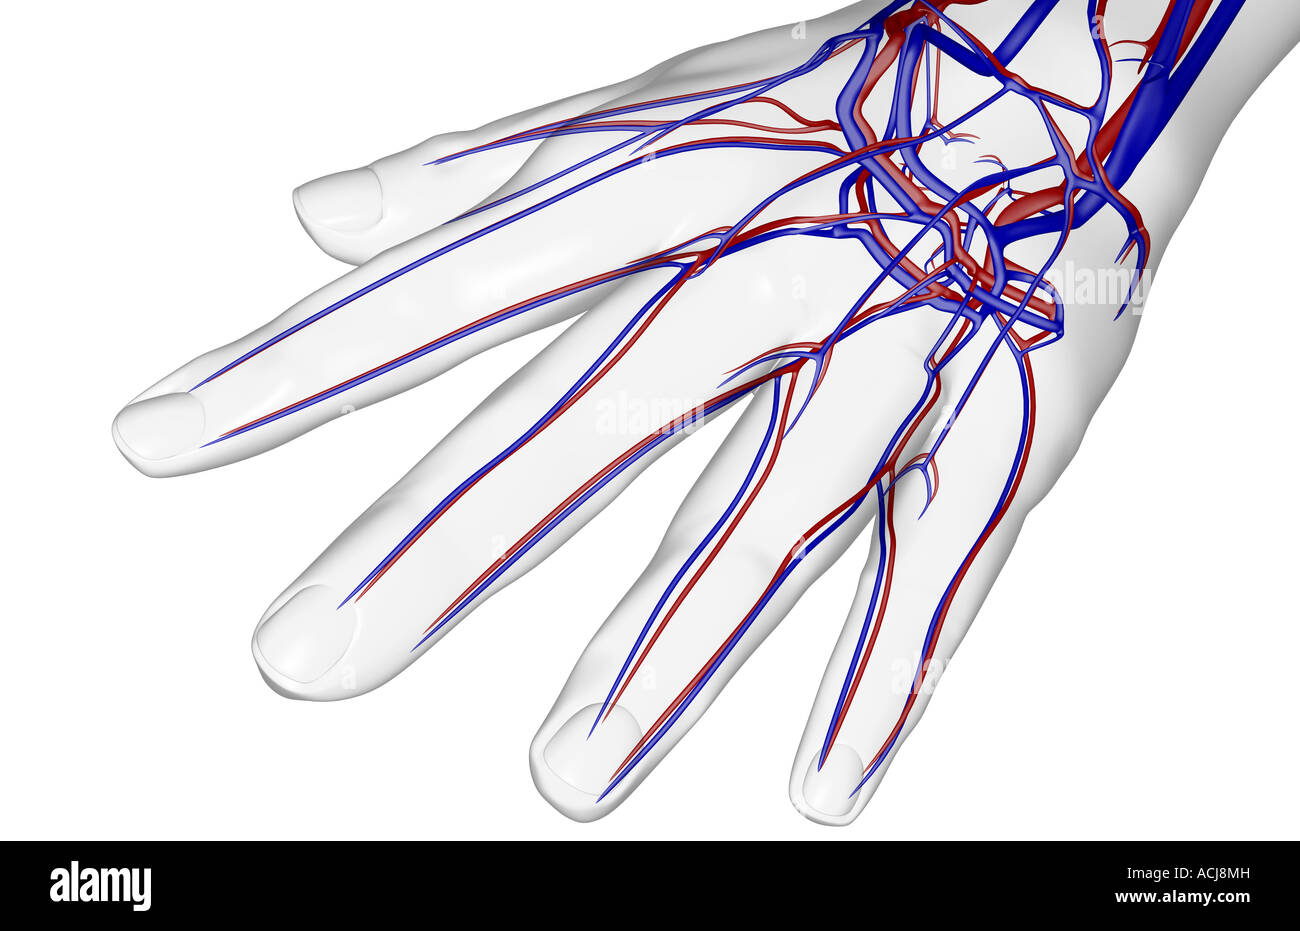

The blood supply of the hand Stock Photohttps://www.alamy.com/image-license-details/?v=1https://www.alamy.com/stock-photo-the-blood-supply-of-the-hand-13167856.html

The blood supply of the hand Stock Photohttps://www.alamy.com/image-license-details/?v=1https://www.alamy.com/stock-photo-the-blood-supply-of-the-hand-13167856.htmlRFACJ8MH–The blood supply of the hand